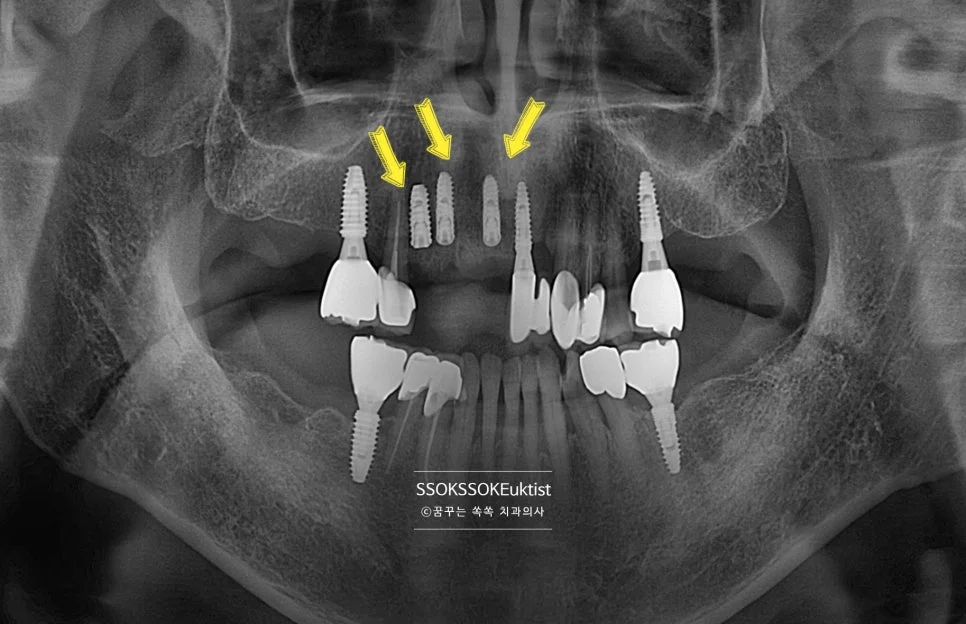

오른쪽 위 앞니 3개는 상당한 충치 그리고 잇몸 염증으로 발치가 필요한 상황입니다. 오른쪽 위 4번째 치아는 이미 뿌리만 남아 있고 뿌리에서는 고름도 나오고 있는 상황입니다.

4개의 치아가 발치가 필요하고, 이를 채우기 위해서 3개의 임플란트 식립을 진행합니다. (발치한 치아만큼 임플란트를 심을 이유는 없습니다)

Step 3. 식립 후 파노라마 확인

식립 후 파노라마 – 3개 임플란트 식립 확인

적절한 위치에, 적절한 각도로, 주변 골보다 2~3mm 깊게 식립되었다면 잘 심긴 임플란트로 볼 수 있습니다.